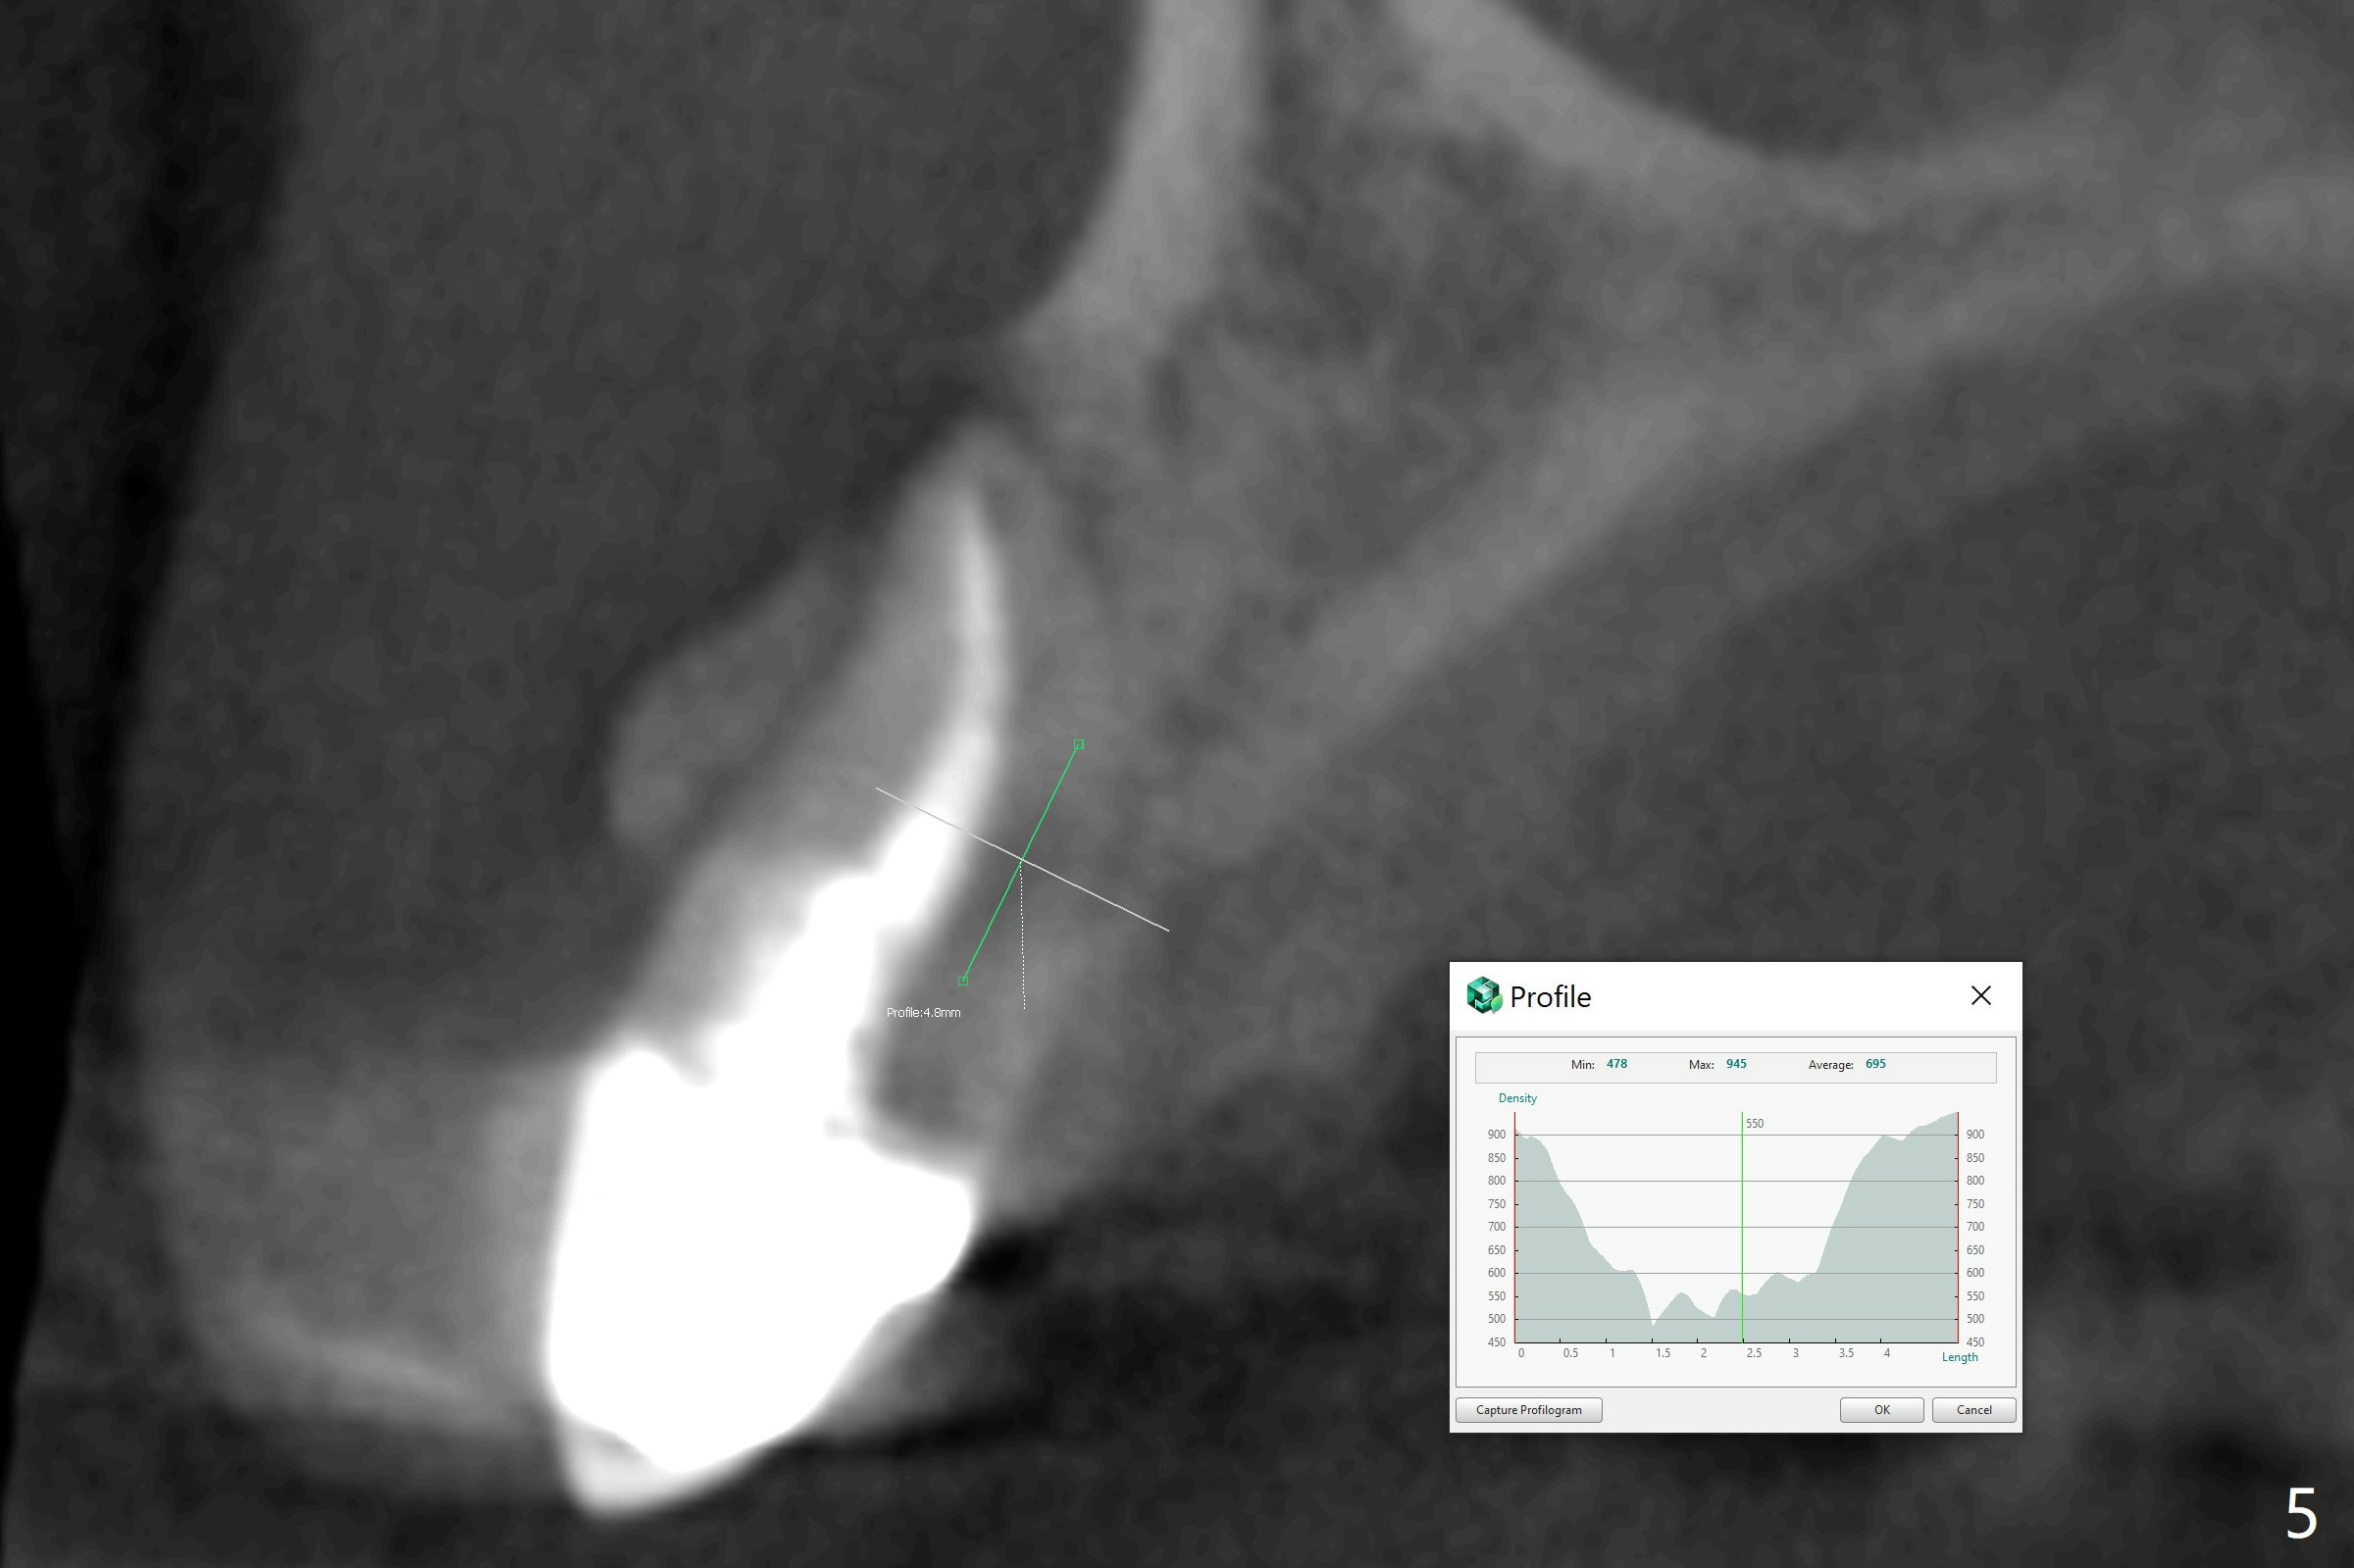

A 56-year-old woman has dislodged #6 crown/post twice in the last 10 years (Fig.1). The root appears to fracture (Fig.2 <), as related to the post (P) and large periapical radiolucency (*). A 3.8x13 mm implant will be placed (Fig.3). PRF membrane and Sticky bone will be inserted while the last drill is in place. Section the root for socket shield. Prepare gingival protection instrument. Reanalysis of CT reveals that the root palatally (Fig.4 *) may cause resorption (<) of the thick palatal plate. The root fracture is supported by profilogram (Fig.5). Therefore the implant should be placed deeper (Fig.6) than that in Fig.3 and shorter if a straight abutment is going to be used (blue (pink: cuff)). In fact the socket is intact when the tooth is extracted. The crown is loose because of post fracture.